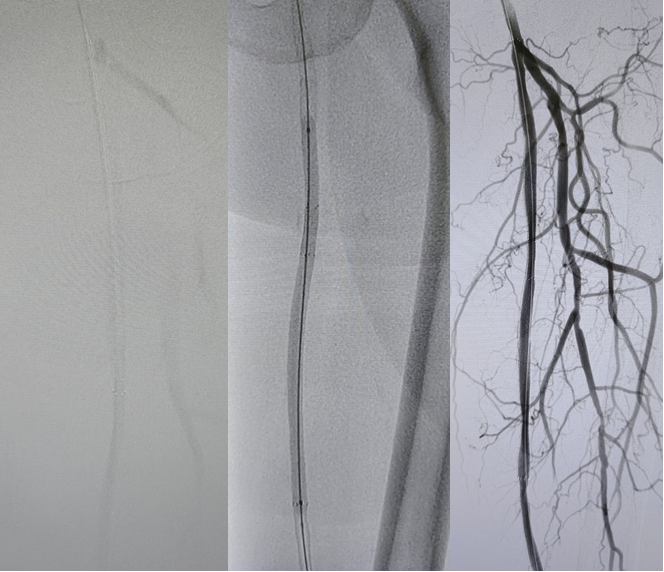

病例1(股腘动脉CTO):

一例重度间歇性跛行患者,导丝通过股腘动脉CTO病变后,若仅凭DSA判断,可能直接进行Rotarex减容。但IVUS检查发现导丝实际位于内膜下(假腔)。此时若进行减容,风险极高。术者遂调整策略,改用球囊扩张后植入Viabahn支架,成功避免了严重并发症。

图:术前造影

图:术前超声

图:Straub Rotarex减容

图:POBA后5-300mmDCB

图:术后造影

图:术后管腔